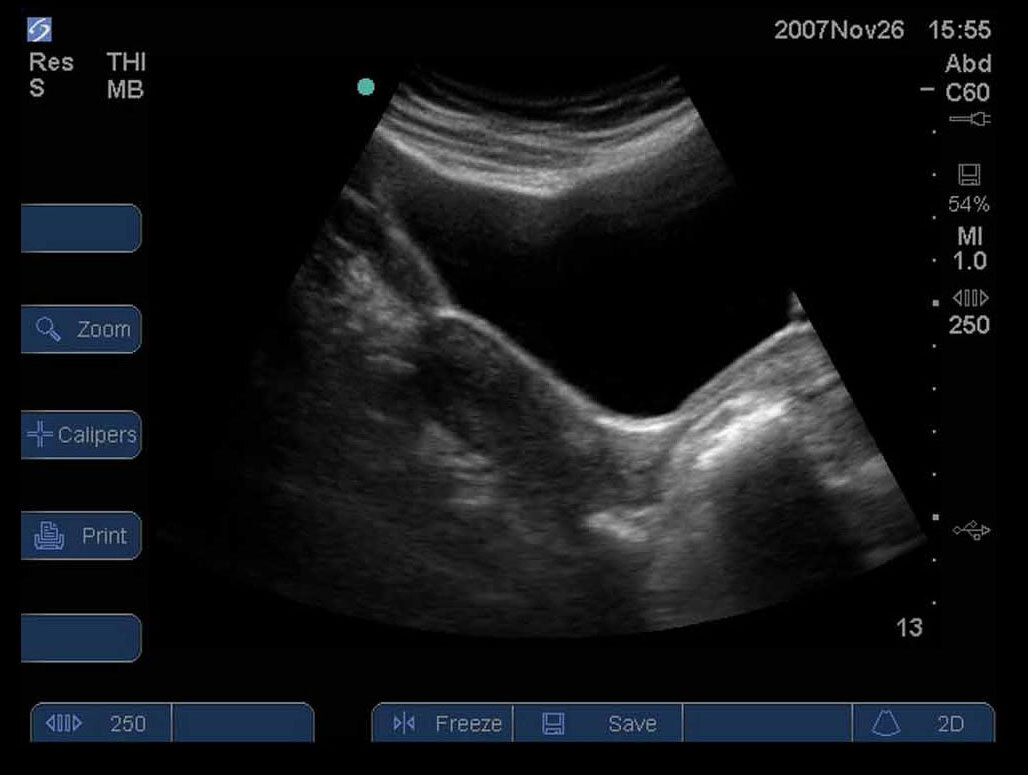

女性の骨盤12画像

S シリーズ:骨盤長軸膀胱および子宮2。